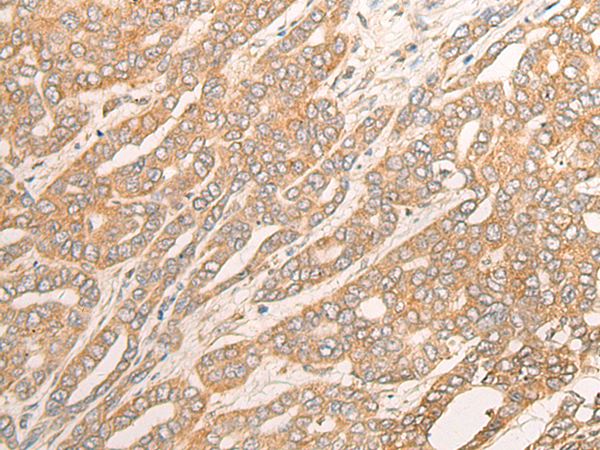

ELISA, IHC |

IHC Positive control: |

Human liver cancer; |

IHC Recommended dilution: |

25-100 |